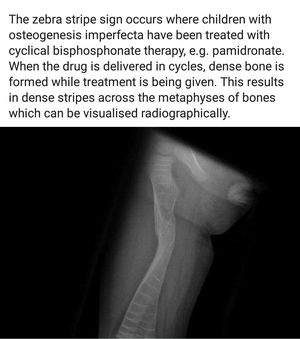

Seen in Children treated with cycles of Bisphosphonate therapy suffering from Osteogenesis imperfecta.